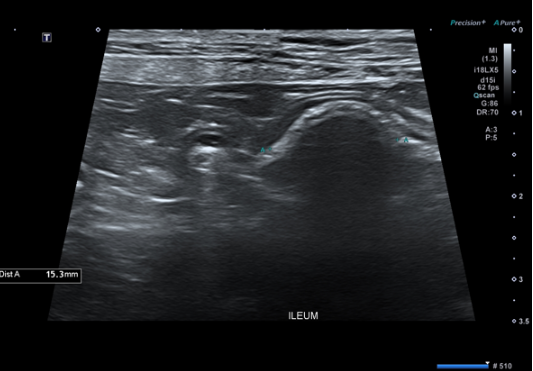

확실한 진단을 위해 복부 초음파 검사를 진행했습니다.

초음파 검사상회장(ileum) 부위에서 소장 내 이물이 명확히 확인되었습니다.